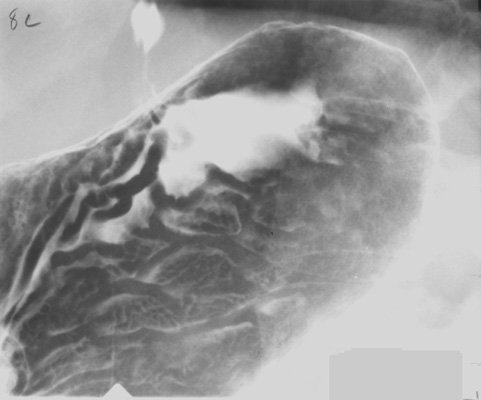

- Gastric body, inferior portion (patient supine, AP)